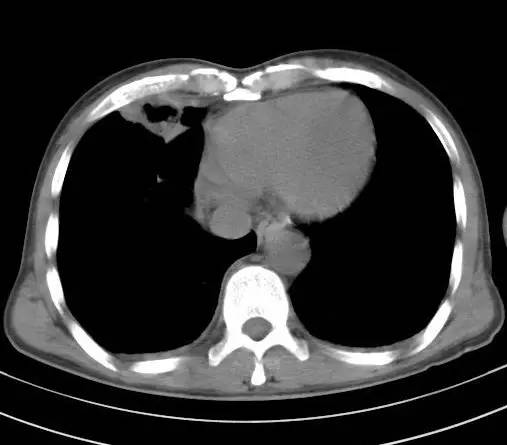

治疗后十天CT(图9-12):双肺病灶明显缩小,有所吸收。

金黄色葡萄球菌肺炎,抗炎治疗23天后完全吸收。